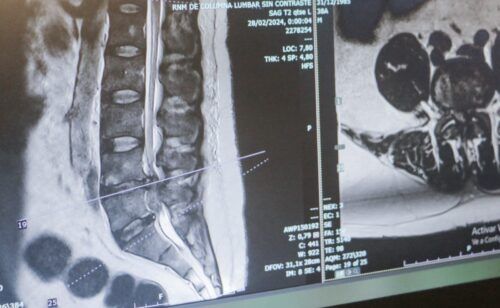

La escoliosis, una alteración en la curvatura de la columna. “Detectarla en etapas tempranas permite evitar su progresión y complicaciones mayores”, señaló.

En paralelo, los avances médicos han transformado las opciones terapéuticas. Procedimientos menos invasivos y tiempos de recuperación más cortos forman parte de la nueva realidad en el tratamiento de estas patologías.

“Hoy podemos ofrecer alternativas más seguras y efectivas, pero cada caso requiere una evaluación individual. No hay soluciones universales”, sostuvo el Dr. Reble.